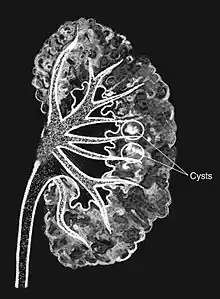

Medullary sponge as seen on an intravenous pyelogram

Medullary sponge kidney is a congenital disorder of the kidneys characterized by cystic dilatation of the collecting tubules in one or both kidneys. Individuals with medullary sponge kidney are at increased risk for kidney stones and urinary tract infection (UTI). Patients with MSK typically pass twice as many stones per year as do other stone formers without MSK. While having a low morbidity rate, as many as 10% of patients with MSK have an increased risk of morbidity associated with frequent stones and UTIs. While many patients report increased chronic kidney pain, the source of the pain, when a UTI or blockage is not present, is unclear at this time. Renal colic (flank and back pain) is present in 55% of patients. Women with MSK experience more stones, UTIs, and complications than men. MSK was previously believed not to be hereditary but there is more evidence coming forth that may indicate otherwise.[1][2]

Classically, MSK is seen as hyperechoic papillae with clusters of small stones on ultrasound examination of the kidney or with an abdominal x-ray. The irregular (ectatic) collecting ducts are often seen in MSK, which are sometimes described as having a "paintbrush-like" appearance, are best seen on intravenous urography. However, IV urography has been largely replaced by contrast-enhanced, high-resolution helical CT with digital reconstruction.[8]